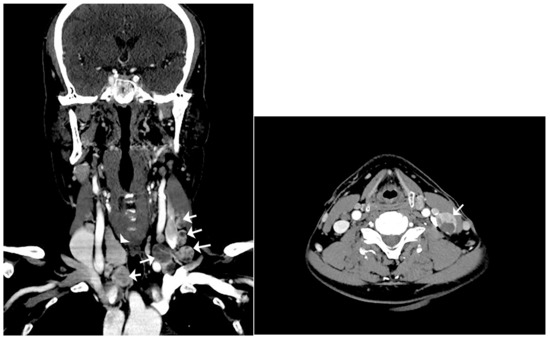

Figure 2.

Computerized tomography (CT) scan of the neck. Left: coronal CT scan of the neck reveals multiple enlarged lymph nodes with internal variable cystic change involving bilateral neck of right level III and left levels II, III, and IV, and right lower cervical chain (arrow: multiple enlarged lymph nodes with cystic change; arrowhead: right lobe of thyroid). Right: axial CT scan of the neck reveals an enlarged lymph node with internal cystic change at left level III (arrow: the most enlarged lymph node with cystic change). Therefore, total thyroidectomy and cervical lymph node dissection were performed to distin-guish lymph node metastasis of occult thyroid cancer from seeding of thyroid tissue due to pre-vious thyroid surgery. Resected bilateral cervical lymph nodes were enlarged to the maximum dimensions of 3.5 × 1.7 × 1.0 cm. The cut surface of the lymph node and thyroid gland showed multiple variable-sized pale tan to brown solid nodules with cystic changes (Figure 3).